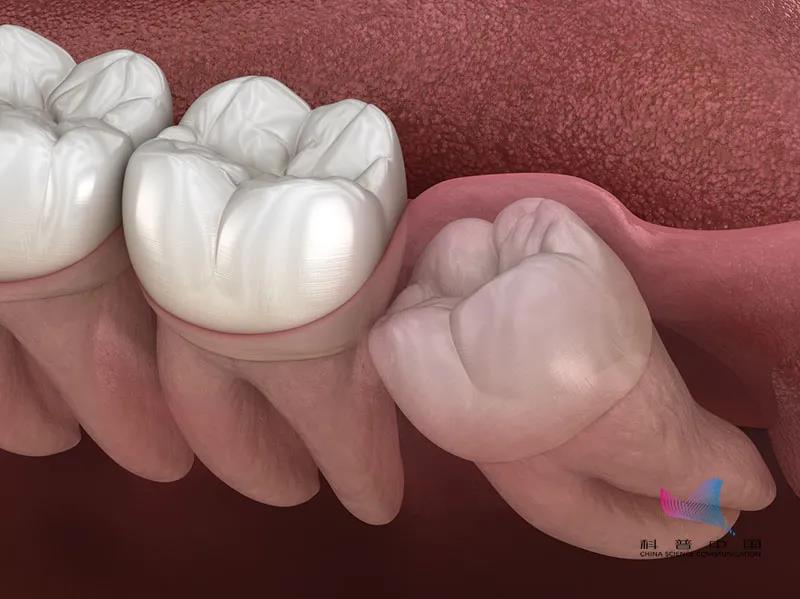

8、除了第3磨牙与多生牙,一般成人拔牙后均需安装假牙,大约拔牙后3个月左右应修复,以避免邻牙倒伏,从而在牙列中引发多米诺骨牌效应!